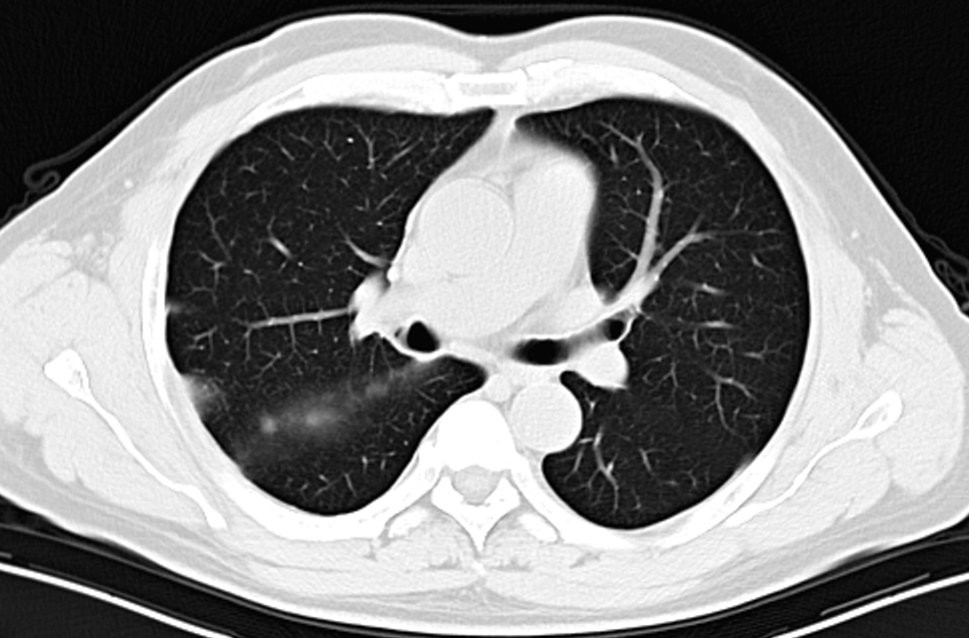

2022-3-6入院复查胸部CT见右肺上叶病灶增大,评价为病情进(PD),予以行胸部SBRT治疗,总剂量40Gy/8Fx。

其实到四线治疗的药物并没有太多选择,免疫治疗推荐:纳武利尤单抗联合伊匹木单抗,考虑到药物的价格及可及性(患者承受不起),患者考虑其他的免疫治疗方法。患者既往使用培美曲赛获得了40个月的PFS,联合免疫可能会有更好的治疗效果。采用立体定向放疗,除了可以更好的控制疾病以外,更多的考虑可以杀死肿瘤细胞,改善肿瘤微环境,释放肿瘤相关抗原,诱导远隔效应的产生。

放疗结束后予以培美曲赛+替雷利珠单抗治疗(培美曲塞0.9g d1+替雷利珠单抗200mg)治疗,现维持治疗至今(2022-8-20)。